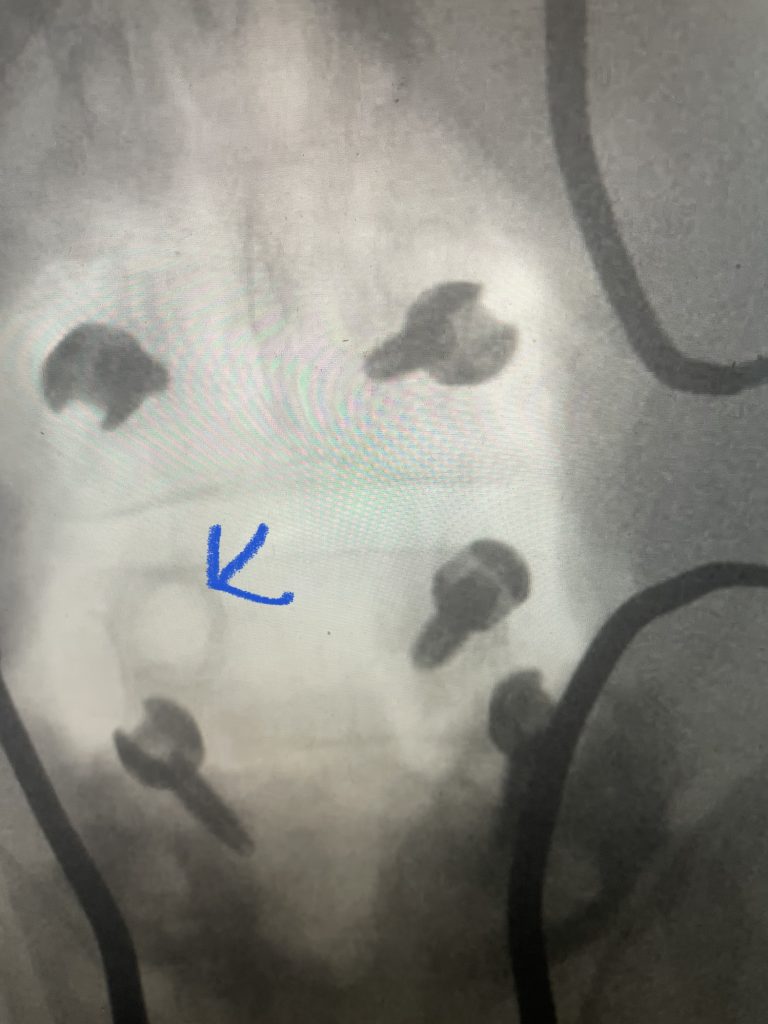

Fig 6: Plain AP x-ray demonstrating a lucency around the L4 screw (red arrow). Note the paucity of bone at the L4-5 level (blue dash) compared to below at L5.

The patient also had a retrolisthesis at L3-4 with mild stenosis. It was also noted that he had lucencies around the L4 screws, suggesting a pseudoarthrosis at L4-5. which is a lack of bony fusion (Fig 6). Patient was had failed conservative management and was taken to the operating room where his construct was explored. There was a complete lack of bony fusion mass between L4 and L5 and the screws were loose. Interestingly the L5-S1 region had a solid bony fusion where we had used BMP, but the L4-5 region did not. We removed the construct and removed the remnant of L4 lamina and the inferior processes and decompressed from L3 to to L5, decompressing well the L4 and L5 nerve roots. We placed new instrumentation from L3-5 with the use of BMP which was discussed with the patient prior to surgery (Fig 7). We also felt it was necessary because of the failure of the fusion. Post operatively the patient had an uneventful course with significant improvement of his prior symptoms.

Fig 7: Intraoperative fluoroscopic AP image of the new construct from L3-5. Note the very large lucency around prior L4 screw